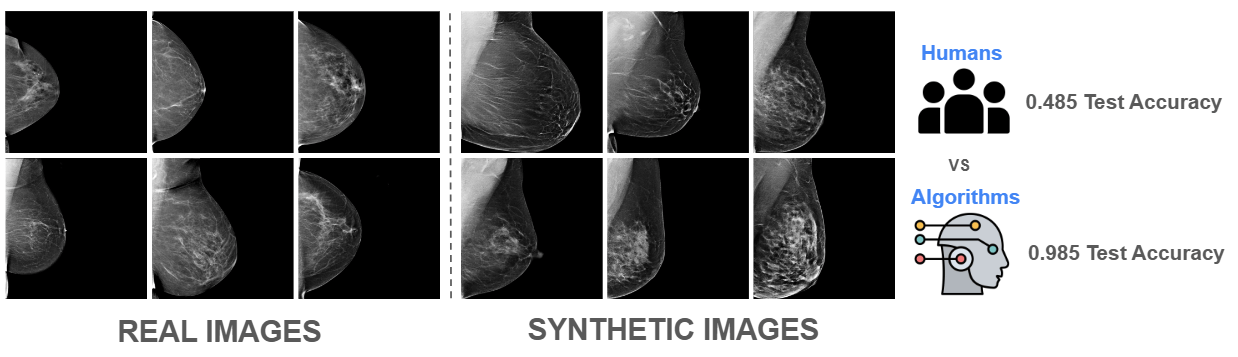

Synthetic Classifier